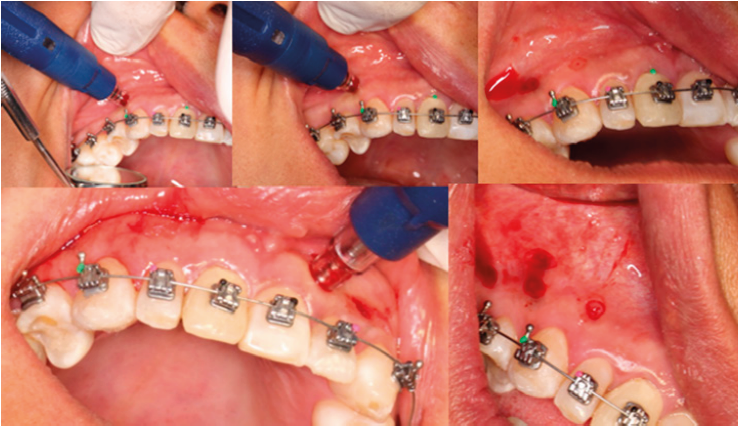

Tras 10 meses de ortopedia, se procedió a la colocación de aparatología de autoligado pasivo, con tubos en segundos y primeros molares. Se colocaron arcos CuNiTi 0.014” en ambas arcadas. No se realizaron extracciones. Se decidió realizar nuevamente MOP´s en las zonas interproximales del hueso alveolar para inducir la formación de hueso y acelerar los movimientos dentales. Dichas perforaciones se realizaron tres veces entre los dientes 13 y 23 (Figura 5), con una profundidad de 7mm. Posteriormente se colocó un arco 0.016” de acero inoxidable, con omega en mesial de molares superiores para proinclinar incisivos superiores, y se colocó cadena elástica para cierre de espacios inferiores y retroinclinación de incisivos inferiores. Después se colocó un arco CuNiTi 0.014”x 0.025” superior y 0.018”x 0.025” inferior con ligadura en bloque de los dientes 12 a 22. Se colocó cadena y resorte abierto para mesializar caninos superiores y elásticos en vector Clase III de 3.5 Oz.

Figura 5 Fotografías intraorales donde se observa el procedimiento de MOP´s en zona interradicular de 13-23.